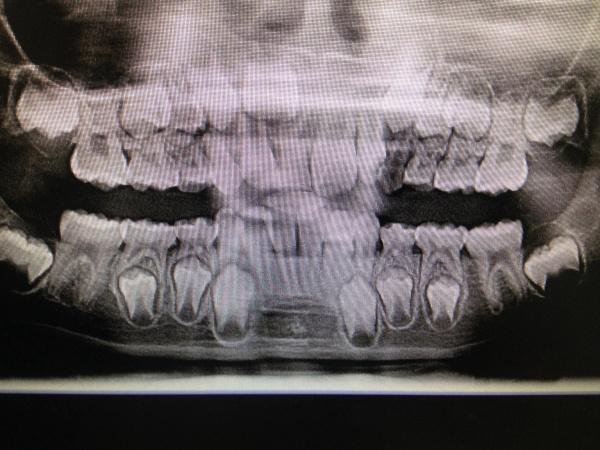

男,9岁10个月,右侧中切牙乳牙未换,右侧切牙已换。牙片显示右中切牙恒牙位置异常,与右侧切牙(恒牙)部分重叠,且右中切牙恒牙牙根稍短小(位置影响?),如何处理?能否矫正?